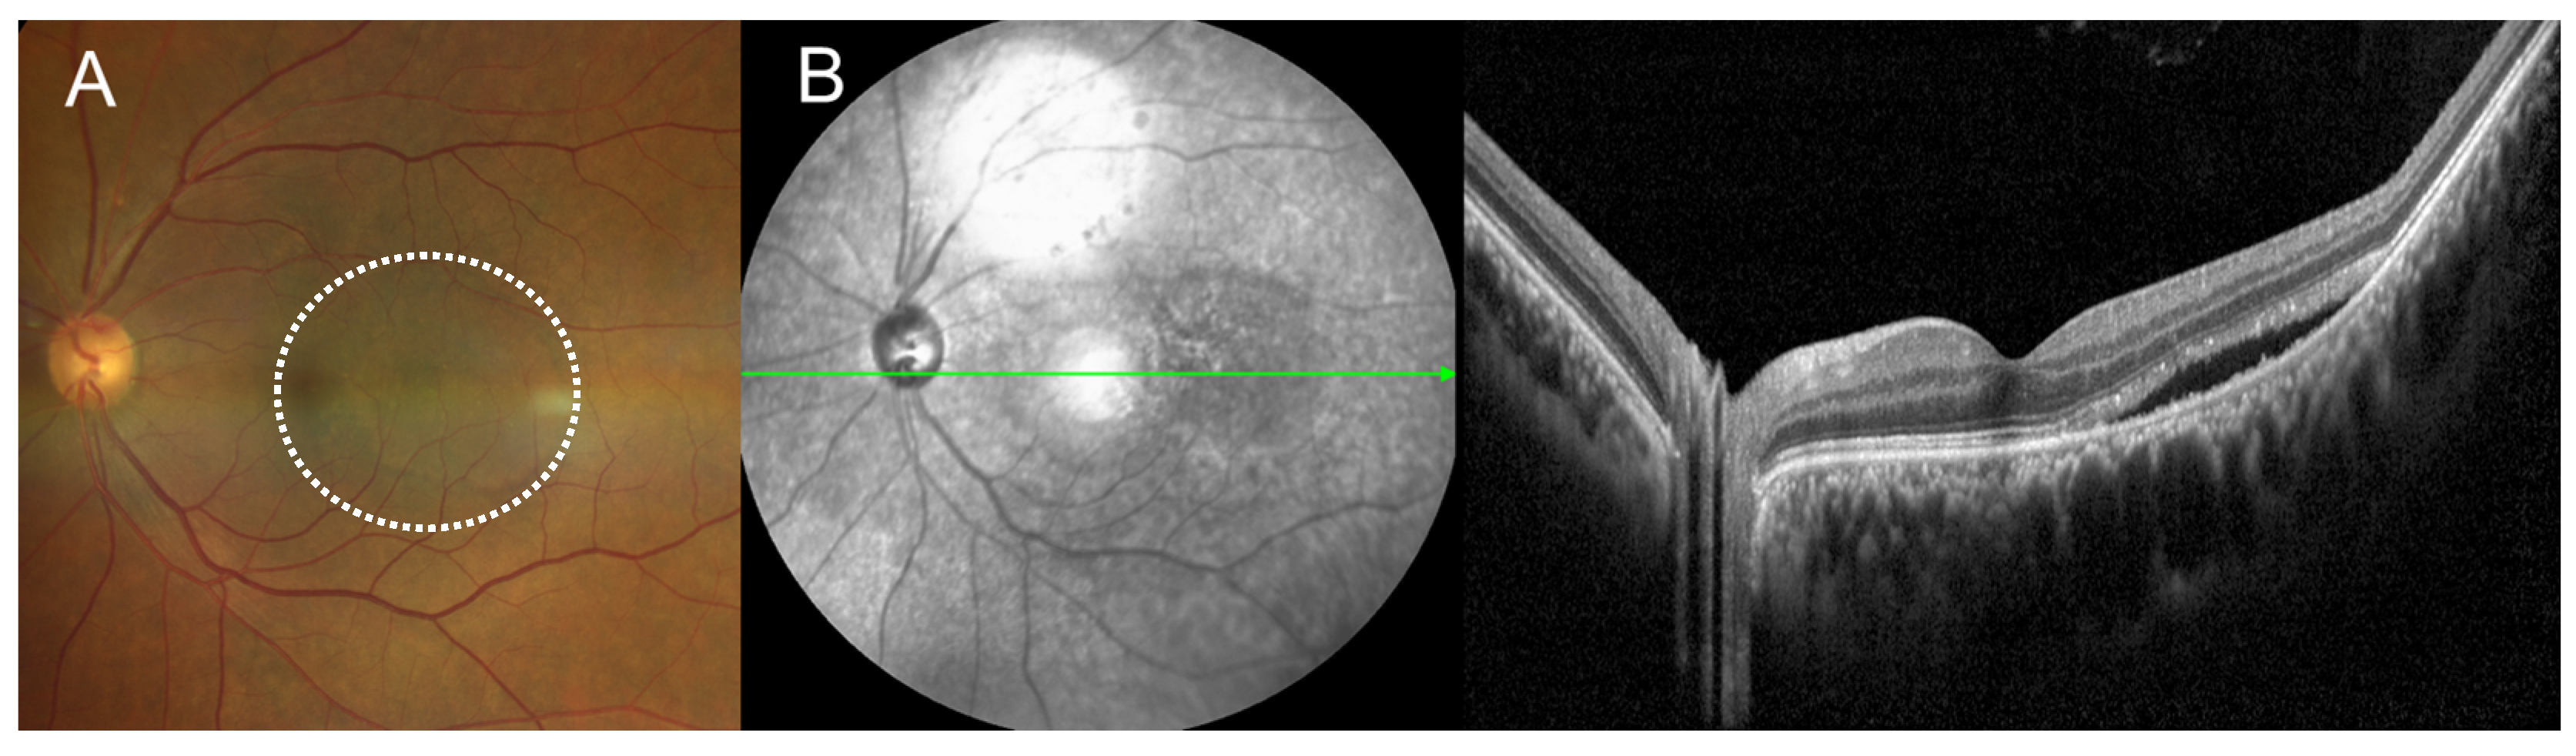

2. Case Presentation